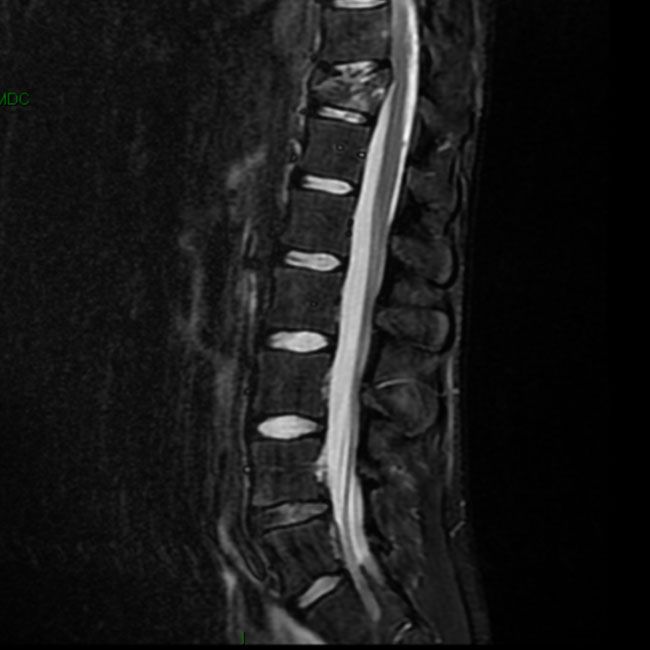

Traumi vertebromidollari

• La patologia traumatica spesso richiede il"blocco"delle vertebre fratturate(mediante viti,barre,placche,"gabbie"),a volte dopo averle riportate nella loro naturale e corretta posizione.In particolare, il caso 1 mostra una lussazione completa della sesta sulla settima vertebra cervicale:dopo una riduzione dello scivolamento tramite un intervento posteriore ed una trazione dell'asse testa/collo,si è provveduto ad un intervento anteriore di "blocco" delle vertebrefinalmente riallineate riallineate , mediante osso autologo,placca e viti in titanio.il caso 4 mette in evidenza una rarissima situazione patologica di rotazione della prima vertebra cervicale sulla seconda (la freccia disegnata mostra la direzione).Questo caso è stato pubblicato su una rivista scientifica ,per la sua eccezionalità.Dopo il riallineamento mediante trazione delle vertebre ruotate , si è provveduto alla stabilizzazione della testa e delle prime vertebre cervicali mediante osso autologo, materiale osteoinduttore ,sistema di stabilizzazione in titanio, grazie ad un intervento condotto per via posteriore